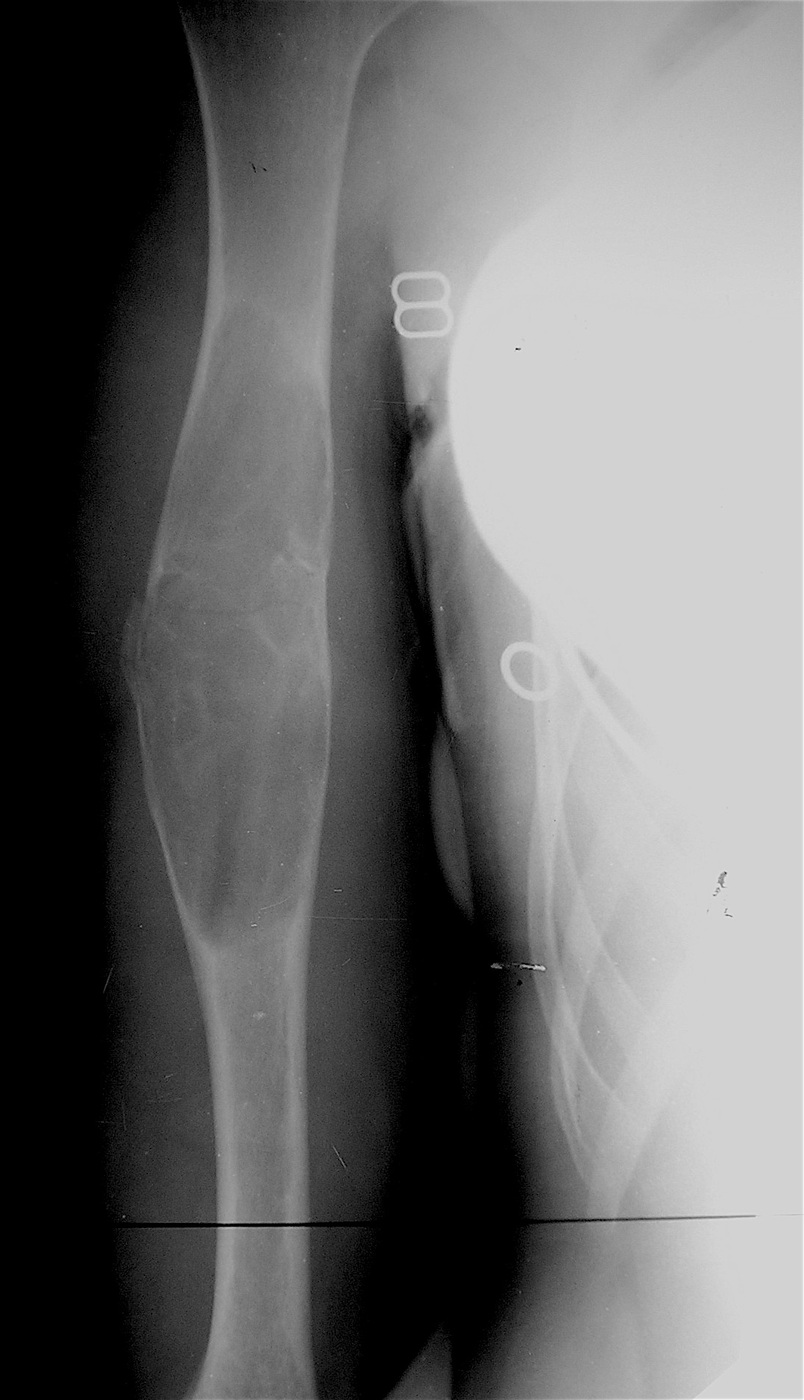

Функция конечности сохранена, ребенок себя обслуживает.

Имеется укорочение правой верхней конечности  на 1,5 см за счет плеча.